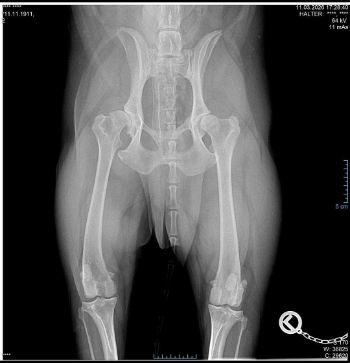

Den Er ist erst 6 J. geworden u.benötigt eine neue Hüfte .Bis dahin bekommt er Spritzen gegen die Schmerzen und Entzündungen.Kann nur sehr kurze Strecken gehen noch und ist ein ganz großer Rückhalt für meinen Bruder der an Asbergersyndrom (leichte Form)leidet.